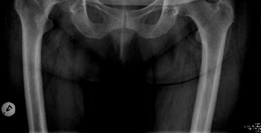

- True Anteroposterior (AP) Pelvis: Standardized view (patient supine, feet internally rotated 15 degrees) to assess joint space, osteophytes, subchondral changes, femoral head migration, bone quality, and pelvic landmarks. Templating for acetabular component size and position is performed.

Clinical & Radiographic Imaging